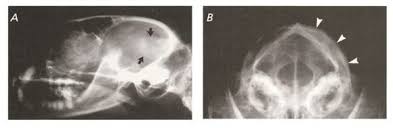

When cells grow old, they die, and. Brain and spinal cord (also known as central nervous system, or cns) tumors can be benign or malignant. Of those tumors, roughly 60,000 are benign, and about. When removed, benign tumors usually do not grow back, whereas malignant tumors sometimes do. Benign brain tumors grow slowly and tend not spread from the original growth site. Primary brain tumors seen in dogs and cats include meningioma, glioma, choroid plexus papilloma, pituitary adenoma or adenocarcinoma, and others. Brain tumor definition a brain tumor is an abnormal growth of tissue in the brain. Clinical signs depend heavily on the size and location of the tumor. Unlike cancerous tumors, they don't spread (metastasize) to other parts of the body. They cannot spread or invade other parts of your body. How common are brain tumors? A tumor of brain is collection of uncontrolled. There are two main types of tumors: